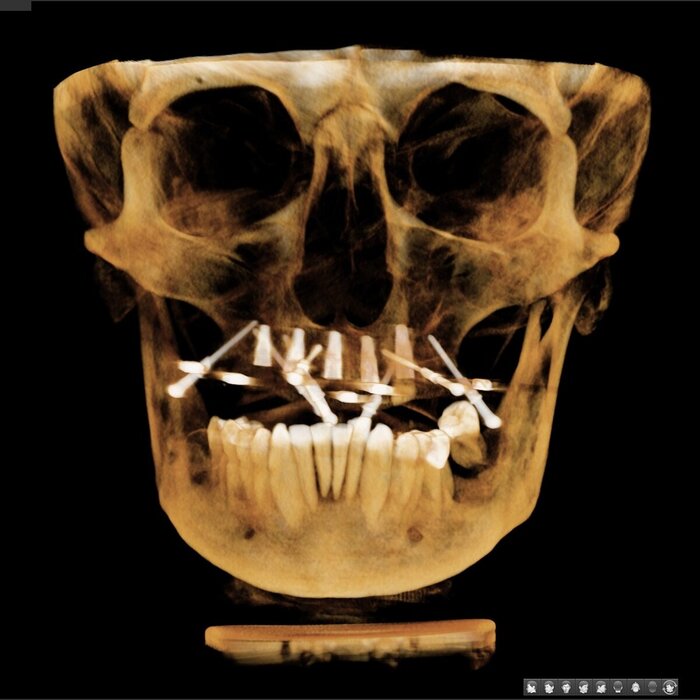

Делаем КЛКТ.

3Д визуализация костей черепа.

Так, мне уже всё понятно - хронический генерализованный пародонтит тяжёлой степени тяжести.